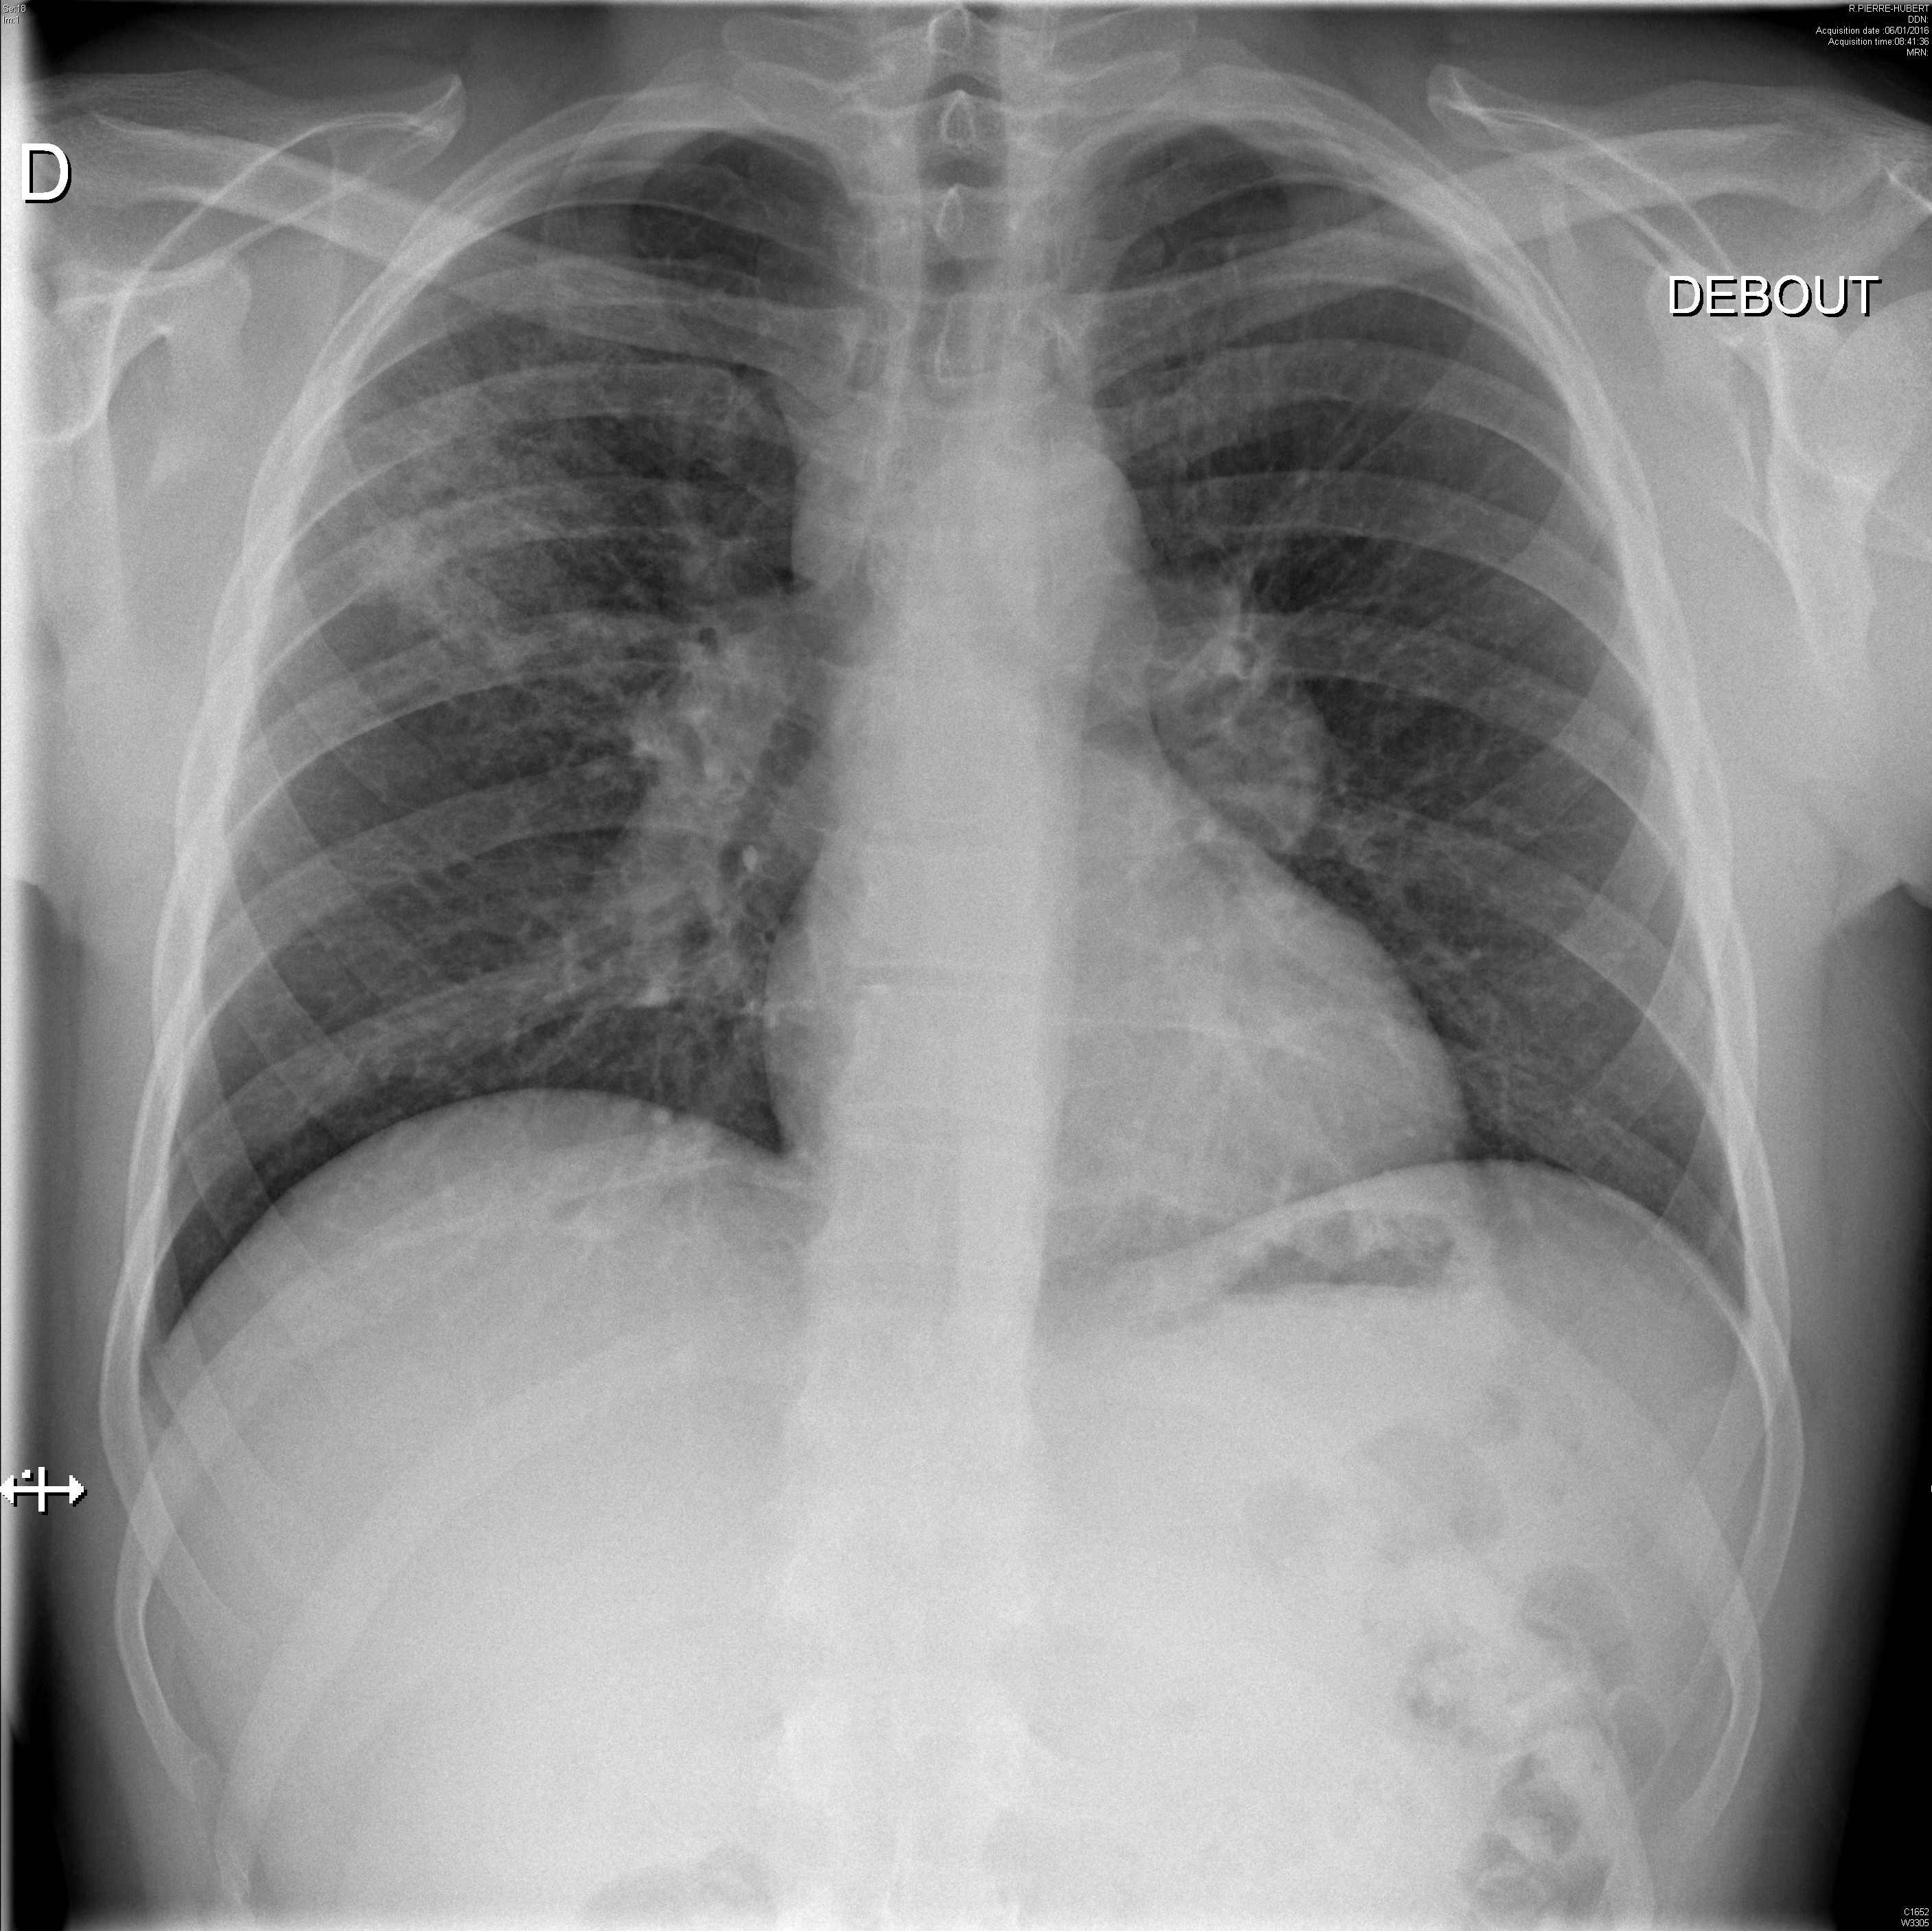

Miliaire pulmonaire dans le cadre d'une sarcoïdose

Syndrome interstitiel et adénopathies médiastinales dans le cadre d'une sarcoïdose systémique